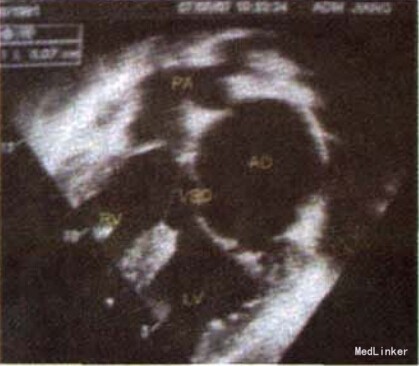

查体:心尖搏动位于胸骨右缘锁骨中线第5肋间,弥散,有抬举感,剑突下可见心脏搏动,心界明显增大,胸骨右缘3、4肋间可闻及3/Ⅵ级吹风样收缩期杂音,剑突下可闻及舒张期隆隆样杂音,S1增强,P2亢进,无震颤; x线胸片示双肺纹理增多,心脏居右侧胸腔,心尖朝向右下方;左肺见水平裂影,心胸比率0.67。 M型超声心动图示LA4.4 rm,EF 0.52;心脏位于右胸腔,室间隔上段回声中断直径3.1,双向分流,二尖瓣环内径4.6cm, 瓣尖开放受限,乳头肌显示不清;肺动脉峰值流速1.9m/s,三尖瓣收缩期湍流频谱4.4m/s,压差76.7mmHg,心尖四腔切面左房经二尖瓣入左室血流束宽约0.6 cm。 导管造影心室右袢,肺总动脉、左、右肺动脉发育可,左弓左降,室间隔缺损位于膜部,右室流出道狭窄,QS:QP为1:2.右心室中压力80/0 mmHg,肺总动脉压力48/27 mmHg;导管通过畸形二尖瓣到达左房困难,二尖瓣造影效果不佳,未能完全描述二尖瓣形态病变。